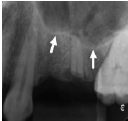

Marque a alternativa que apresenta o reparo anatômico destacado na imagem abaixo (setas):